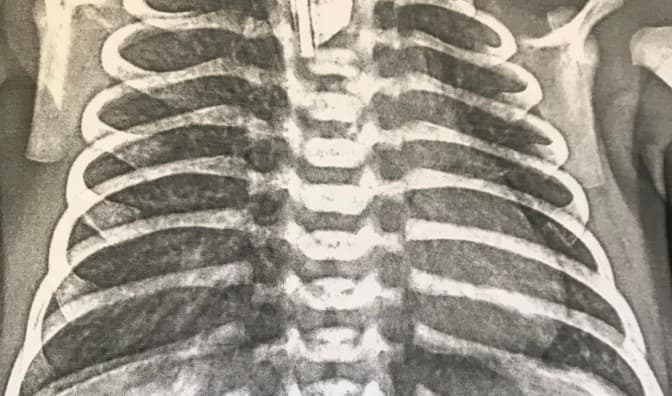

Місяць тому мама звернулася до львівських лікарів, які й провели дитині реконструктивну операцію – замінили власний стравохід кишковим трансплантатом. Штучний стравохід вони сформували з фрагмента товстого кишківника, розмістивши його за грудиною від шлунка до верхнього сегмента стравоходу. Уже на третій день після операції Оля почала самостійно ковтати слину, а через тиждень – пити воду. Дівчинку вже виписали додому і до лікарів вона їздитиме лише на планове обстеження.

Нагадаємо, що хлопчику Данилку, який має важку ваду розвитку – атрезію стравоходу, вже переніс кілька операцій, проте, щоб жити йому потрібна операція – формування «штучного стравоходу», що передбачає переміщення частини кишківника з черевної порожнини у грудну клітку.